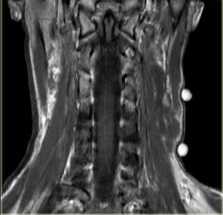

(Слева) КТ с КУ, аксиальная проекция. Образование овальной формы в заднемедиальном отделе сонного пространства. Обратите внимание, что сонная артерия находится на передней поверхности опухоли, а внутренняя яремная вена - на латеральной. Незначительное накопление контраста не очень характерно для шванном, в данном случае вид опухоли напоминает нейрофиброму.

(Справа) MPT Т2ВИ, аксиальная проекция. Округлое образование с неоднородным сигналом, которое смещает общую сонную артерию кпереди. Внутренняя яремная вена смещена вместе с артерией. При сдавливании яремной вены ее идентификация может быть затруднена.